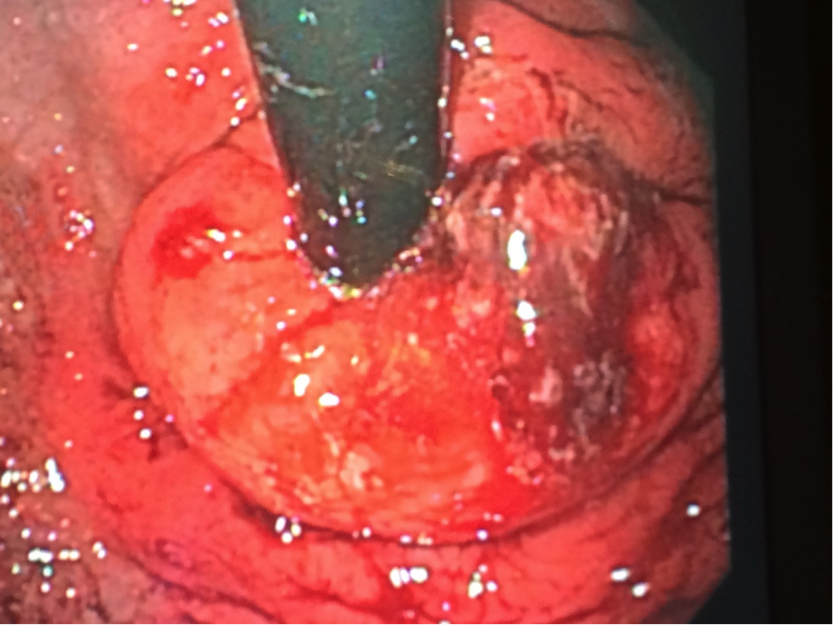

We are pleased to offer a new, exciting treatment option: transoral incisionless fundoplication (TIF). This is a procedure done entirely through the mouth, with no need for incisions. The TIF procedure reconstructs an antireflux valve at the gastroesophageal junction and reduces hiatal hernia, restoring natural anatomical geometry. The procedure generally takes less than one hour; most patients can go home the next day and return to work and most normal activities within a few days.